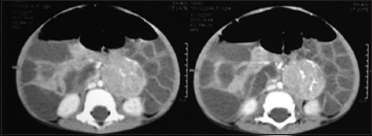

A 20-month-old girl child was admitted with complaints of watery diarrhea of 3-month duration. Diarrhea was associated with abdominal distension and documented weight loss. The loose stools were watery, 5–6 times a day, not associated with blood or mucus. As there was an increase in the frequency of loose stools associated with decreased urine output and lethargy for 1 day, she was brought to us. On examination, the child was hypotonic, undernourished, and weighing 7.8 kg. Signs of some dehydration were present, and the abdomen was distended. Laboratories done at admission showed severe hypokalemia (1.8 mEq/dl), metabolic acidosis (11 mEq/dl), and normal chloride (100 mEq/dl). The child's dehydration was corrected with isotonic saline, and potassium infusion was given under cardiac monitoring. Serial monitoring of serum electrolytes was done. During the hospital stay, diarrhea persisted and serial laboratories showed persisting hypokalemia (<2 href="https://www.thieme-connect.com/products/ejournals/html/10.4103/ijmpo.ijmpo_15_18#FI90451-1" xss=removed>Figure 1] confirmed a 37 mm × 38 mm × 49 mm heterogeneous mass lesion in the left para-aortic region below the left renal vessels. Bone marrow biopsy showed trilineage hematopoiesis. Laparotomy and in toto excision of tumor mass were done. Histopathology of the tumor mass was consistent with ganglioneuroblastoma-mixed nodularity of Schwannian stroma-poor type. N-Myc amplification was negative. After tumor removal, diarrhea settled, hypokalemia and acidosis improved, and there was documented weight gain.

| Figure 1 Computed tomography abdomen showing heterogeneous mass lesion with calcification in the left para-aortic region